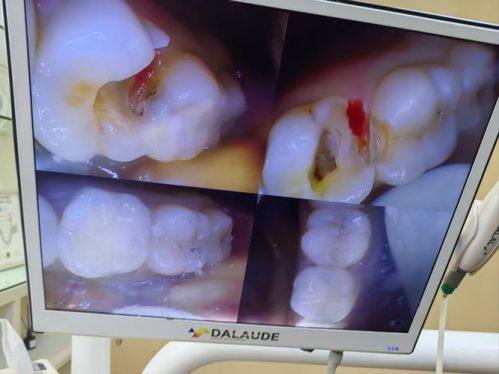

3. 口腔修复:针对牙齿缺损、缺失等问题,提供专精的修复方案,使牙齿修复正常功能和外观。

9. 根管治疗:500 - 1500元